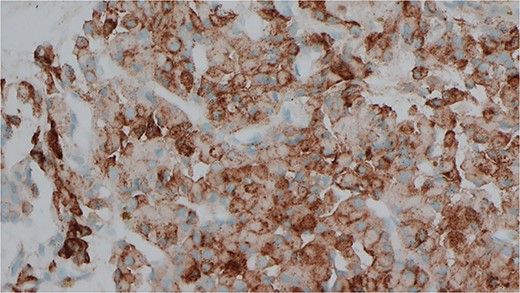

She was subsequently referred to our service for further surgical evaluation. At the time of referral, she was asymptomatic. Initial blood tests showed an elevated PTH of 1256 pg/ml (range 15–65 pg/ml), reduced adjusted calcium of 2.05 mmol/l (range 2.21–2.52 mmol/l), normal free T4 at 19.9 μg/dl (range 12–22 μg/dl), and a reduced TSH <0.01 mU/l (range 0.27–4.20 mU/l), along with a raised phosphate of 2.32 mmol/l (range 0.81–1.45 mmol/l). A CT neck showed a large left thyroid mass with a differential diagnosis of metastatic lymphadenopathy versus a parathyroid adenoma. She underwent an ultrasound and fine needle aspiration of the thyroid mass, which revealed a Thy3A lesion with no evidence of malignancy. Following further multidisciplinary team (MDT) discussion, an immunostain for PTH was performed on the EBUS TBNA, which revealed that the oncocytic cells were positive for PTH (see Figs 1 and 2). This was confirmed by a sestamibi scan, which confirmed a sestamibi-avid nodule (see Fig. 3).

Immunocytochemical stain for PTH which is positive in the cells from EBUS biopsy.